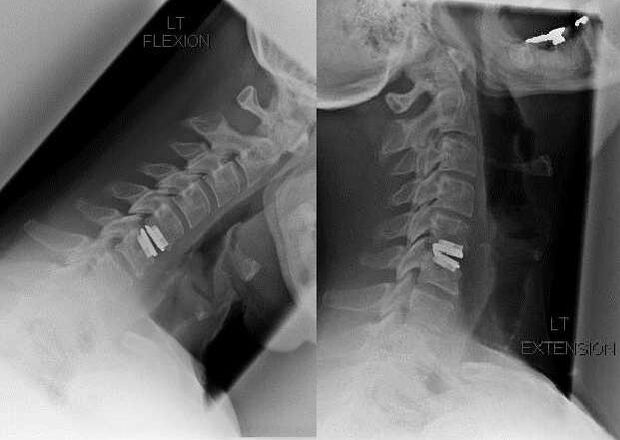

Indikacije za kiruršku intervenciju uključuju neučinkovitost konzervativnog liječenja, kao i komplikacije cervikalne osteohondroze, na primjer, diskogenu mijelopatiju, sindrom vertebralne arterije i radikularni sindrom. Za dekompresiju leđne moždine, krvnih žila i korijena kralježnice provode se sljedeće operacije:

Tijekom operacije mogu se izrezati fragmenti kosti i ligamenti, a intervertebralni diskovi mogu se potpuno ili djelomično ukloniti. Za male hernialne izbočine često se provodi laserska vaporizacija jezgre diska.

Nakon ekscizije vertebralnih struktura često je potrebna stabilizacija segmenata pokreta kralježnice spinalnom fuzijom ili ugradnjom koštanih i dermalnih autotransplantata.